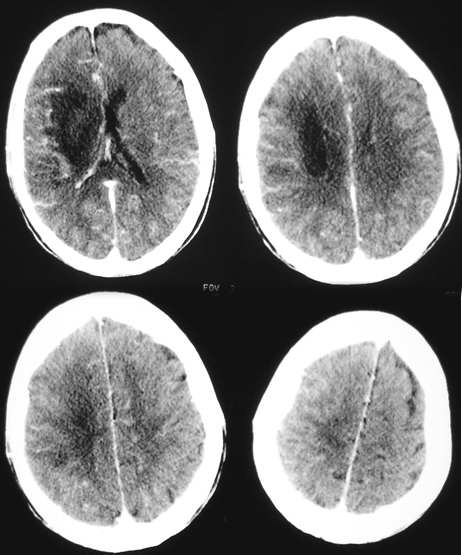

[emb6]右侧基底节区脑梗塞,占位效应明显(肿瘤不除外);建议跟踪复查。

[emb6]右侧基底节区脑梗塞。

ct增强未见低密度灶强化,应该是右侧基底节区脑梗塞并脑水肿。

右侧基底节区脑梗塞

右侧基底节区脑梗塞,伴脑水肿

考虑1~2星型细胞瘤